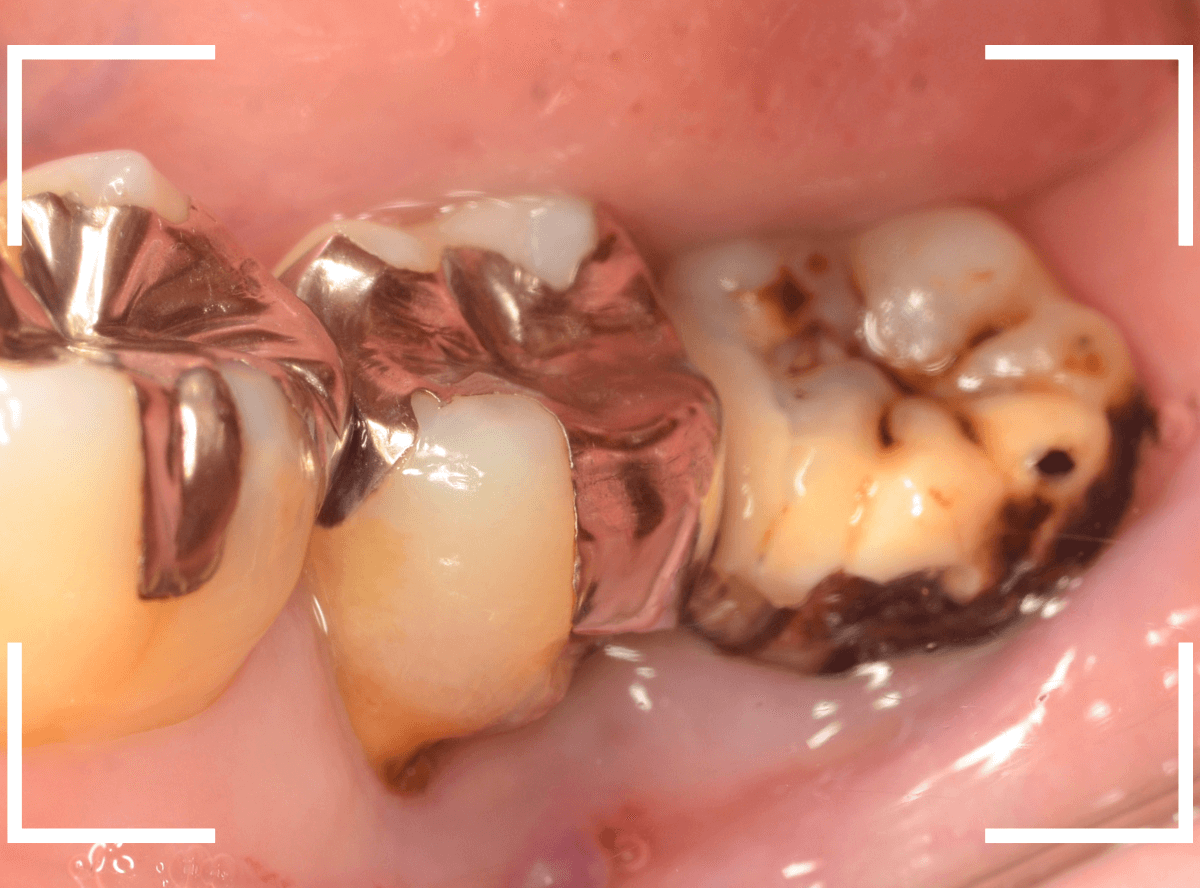

Case.2 放置してボロボロの歯

今回は、虫歯治療途中の歯を放置してボロボロになってしまった歯の抜歯のケースです。

痛みがないせいか、歯に穴が空いたまま長期間放置してしまったために、残念な状況になってしまいました。

以前の先生が治療した際のの状況は詳しくはわかりませんが、

後ろに生えていたおやしらずを抜歯せずに放置してしまったために虫歯になってしまった

→神経の治療の途中で放置したために歯がボロボロになってしまった

という流れかと思います。

本格的に腫れたり痛みが出る前に抜歯する必要があります。